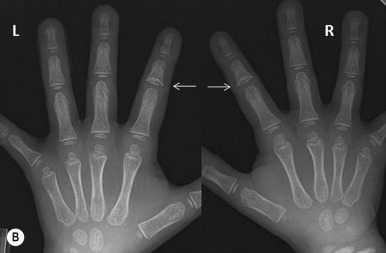

Trichorhinophalangeal syndrome (TRPS) type I is an autosomal dominant disorder characterized by a distinctive facies with pear-shaped nose, elongated philtrum, thin upper lip, supernumerary incisors, and receding chin ( Fig. 7-15 ) and skeletal abnormalities including brachydactyly, deviation of the middle phalanges ( Fig. 7-16, A ), hip malformation, and short stature. Most patients show fine, sparse, slow-growing hair, but almost-normal hair to complete baldness have been described. The underlying molecular basis is mutation in TRPS1, which encodes a transcription factor. Individuals with type II TRPS (Langer–Giedion syndrome) have associated multiple cartilaginous exostoses. The diagnosis is made by the demonstration of cone-shaped epiphyses of the fingers seen on plain radiography ( Fig. 7-16, B ). These findings may not be detectable until 3 years of age or older. The type II form is a contiguous gene syndrome, with deletion of both the TRPS1 gene and the gene that is mutated in multiple exostosis type I ( EXT1 ). Type III TRPS results from mutations in TRPS1 but manifests with much more severe short stature and generalized shortening of all phalanges and metacarpals than TRPS type I.